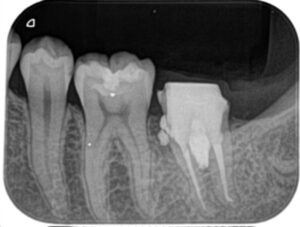

レントゲン撮影を行うと、近心および分岐部に影が映りました。ここは歯に穴(穿孔)が開いており、そこから細菌感染して歯の周りの骨が溶けてしまっています。

被せ物および土台を除去すると肉芽が増殖しており、電気メスで除去。MTAセメントで穴を塞ぎました。

穿孔修復を行った後は痛みが落ち着いたため、根管内の古いガッタパーチャーを除去し、十分に次亜塩素酸ナトリウム水溶液(通称ヒポクロ)で洗浄した後根管充填を行いました。

近心および分岐部の穿孔修復ならびに根尖が壊れていた遠心根をMTAで充填しました。

(近心根は通常のガッタパーチャーで充填してます)